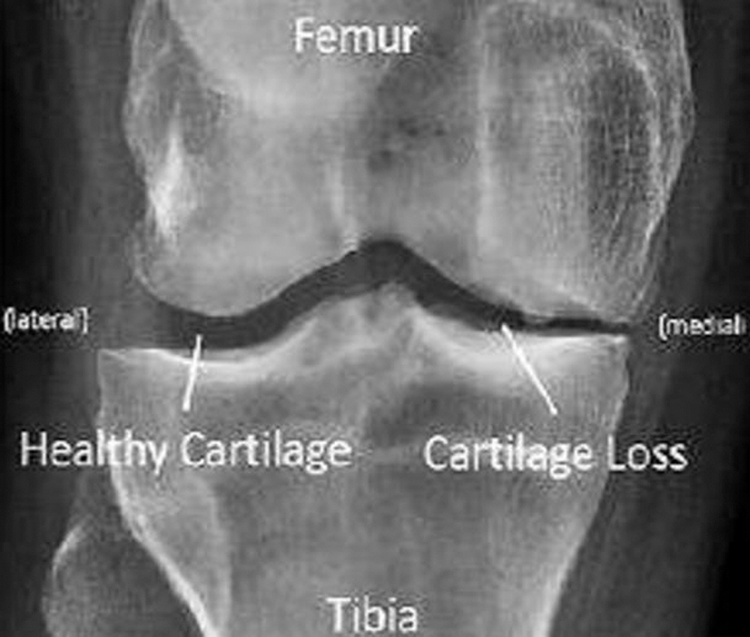

Osteoarthritis is a type of disease that mainly destruct the joint in knee, hip and hand and this disorder may happen when the cartilage cushion down the knee which starts to wear down [1]. Arthritis is joint inflammation which is characterized by joint stiffness which can lead to poor function. This mainly happens to age down and over weighted people. In osteoarthritis there are two main types which can be primary that happens to aged people and the secondary may occur to earlier stage due to injury in accidents, weak body conditions, and some diseases like diabetes. In our paper we are considering a CT image also termed as CT scans; to scan a knee image [2]. CT scan may show the cross-sectional images of knee so that the disorder can be defined clearly through image. The body is circled by a CT scanner and it transfers pictures to a computer. These pictures are used by the machine to create detailed images. This helps the joints, cartilage, ligaments, vessels, and bones that make up the knee to be seen by physicians and qualified technicians. CT images can be introduced with main advantages like quick access of image detection in knee, painless, availability is better compared with MRI scanning; the bones structures are visualized in good view [3]. CT scan may also view an image of a small portion of knee [4]. Fig. 1 shows the CT scan image of knee joint destruction.

Figure 1: CT scan image of knee joint destruction